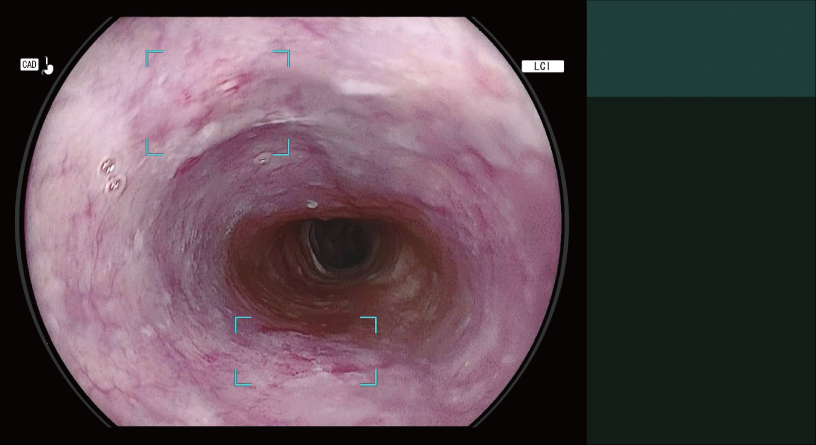

Detects the area that may be oesophageal squamous cell carcinoma and displays it on the main monitor in real-time.

Detection Box

Indicates the area where this software suspects that a lesion is present.

The types of Detection Mode are automatically switched depending on the observation mode selected.

- *2 Detection Mode for Oesophageal Squamous Cell Carcinoma Suspect Area